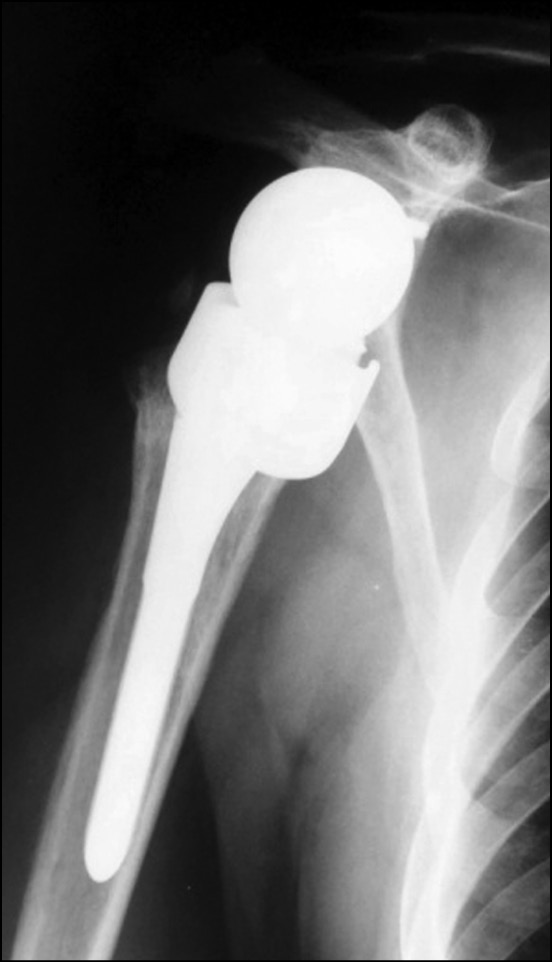

Пациенту с перипротезным переломом диафиза плечевой кости проведена ревизионная операция с целью остеосинтеза диафиза плечевой кости серкляжным способом (рис. 4, 5).

Рис. 5. Рентгенограмма пациента после остеосинтеза перипротезного перелома серкляжным способом

Fig. 5. X-ray of a patient after osteosynthesis of periprosthetic fracture using cerclage technique